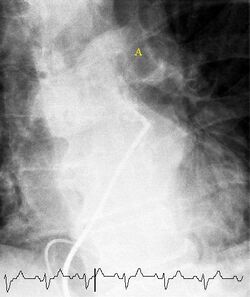

Fluoroscopic pulmonary angiography

Selective pulmonary angiogram revealing clot (labeled A) causing a central obstruction in the left main pulmonary artery. ECG tracing shown at the bottom.

Historically, the gold standard for diagnosis was pulmonary angiography by fluoroscopy, but this has fallen into disuse with the increased availability of non-invasive techniques that offer similar diagnostic accuracy.[69]